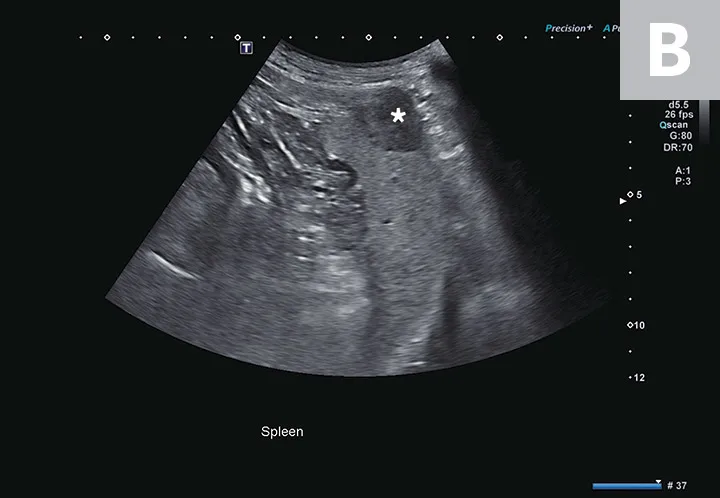

FIGURE 2

Abdominal effusion (A; asterisk) adjacent to a normal spleen (arrow). Abdominal carcinomatosis with secondary neoplastic effusion was diagnosed. Left parasternal short-axis view of a heart with pericardial (B; asterisks) and pleural effusion (arrow).